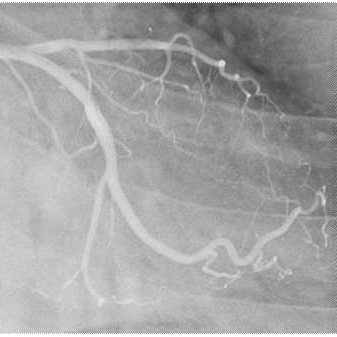

Abnormal Origin of the Right Coronary Artery: A Case Report with Literature Review

Anomalous origin of right coronary artery is a rare congenital anomaly that was 1st described in 1948 by White and Edwards. It is well established that an anomalous origin of right coronary artery may be asymptomatic but it can lead to angina pectoris, myocardial infarction and sudden death, even in the absence of atherosclerosis. So, although many of these anomalies are clinically insignificant but some are associated with serious morbidity. Incidence of coronary anomalies in patients undergoing coronary angiography varies from 0.64% to 1.3%. We described the case of corresponding author, who had history of breathlessness off and on in the early morning in lying down posture relieved on seating posture; and once a moderate pain along the medial aspect of his right arm and then the evaluation revealed an anomalous right coronary artery arising at a higher level. We discussed the clinical importance of this anomaly and reviewed the literature concerning current views and therapy. Conceptual and therapeutic debates remain. Aim of present study is to reappraise the concept of anomalous origin of coronary artery and to discuss the potential hazards and treatment rationale of this anomaly on the basis of literature review. A comprehensive literature review was made.